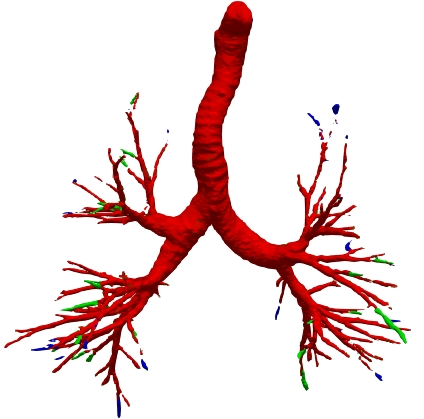

However, current state-of-the-art methods of lung organ segmentation still face several challenges and aspects for improvement. Firstly, the unlimited voxel values, multi-site imaging discrepancy and class imbalance in lung organ images can lead to false-negative and leakage issues in prior segmentation methods, which badly influences the critical early diagnosis of imperceptible lung diseases, e.g., lung fibrosis, nodule and hypertension, etc. Secondly, the presence of numerous slender branches, e.g., bronchioles and arterioles, which are easily lost during the recycled down/up-sampling procedure in Fig. 1, can result in discontinuity, detail loss, and coarse mask predictions. Thirdly, most CNN-based medical segmentation methods treat all points equally during the mask rendering stage, overlooking the vulnerability of border points in Fig. 1 (f) and the importance of explicit border modeling. Lastly, while Vision Transformer (ViT) has shown promise in computer vision tasks [1, 4], its quadratic operation complexity limits its application in 3D high-resolution CT images due to hardware constraints. Meanwhile, most specific datasets for medical image analysis are small and scarce due to laborious manual annotation and privacy protection, which badly restricts the potential of transformer-based top-tier methods.

We qualitatively analyze our method on four challenging lung organ datasets. In Fig. 5, SFCN [19] suffers from severe false positives and some false negatives, especially for the big green areas of airway leakages. WNet [22] is mainly influenced by false negatives on the main trachea. For the Fibrosis dataset at the third row, it also encounters the false negative problem in the terminal bronchioles moderately. FANN [10] bears the slight discontinuity issue of false negative in the terminal bronchioles of BAS dataset, and the severe discontinuity and airway leakage problems on the more challenging Fibrosis benchmark. Instead, due to the above two novel modules, our method can solve the defects of false negative, discontinuity, and leakages faced by past advanced methods. Besides, the results on PARSE22 artery dataset in supplementary Fig. 6 also proves this.

Comparison on fibrosis dataset. Although it’s the very challenging benchmark, our FABR still behaves robustly and exceeds the best method FANN by 3.4% CCFs with a total metrics of 84.39% CCFs, 83.81% IoU, 85.1% DLR, 80.01% DBR. The lowest AMR (7.1%) confirms that our method can solve the discontinuity issue well. Other methods also behave similarly to the BAS dataset. As seen in the two datasets, the main improvements of our method are consistently at the IoU, DLR and DBR metrics, which are mainly influenced by bronchioles and trachea borders that are easily lost due to network down/up-samples. Hence, our method can extract the robust bronchiole features and render border well via the two novel modules for the accurate lung organ segmentation.

Comparison on PARSE22 dataset. This dataset is more challenging due to more dense small bronchioles shown in supplementary Fig. 6. However, our method still reaches the best weighted average multi-level dice of 84.96% in Table 2 compared against some advanced methods via the official evaluation. As you can see, the remarkable gain comes from the “branch artery”, which maintains the consistency with above airway segmentation.